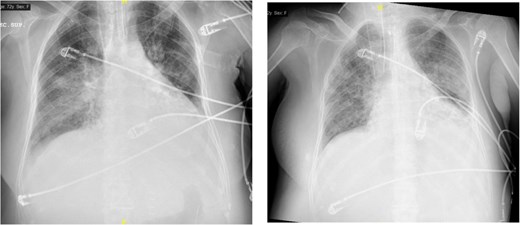

On postoperative day 4, she developed progressive respiratory failure requiring reintubation. Chest imaging revealed right basal consolidation and left pleural effusion, alongside elevated inflammatory markers (Fig. 2). By day 9, after initiation of weaning, new bilateral patchy interstitial infiltrates were observed on radiographs. Acute pulmonary oedema was excluded based on echocardiography findings and lack of diuretic response, leading to a diagnosis of ARDS. Concurrent pancytopenia was attributed to MMC toxicity. The patient improved progressively following corticosteroid therapy.

The image on the left shows right basal consolidation and left pleural effusion, which evolves into bilateral interstitial infiltrates in the image on the right.